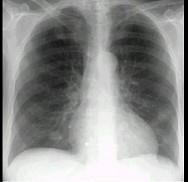

问题 多发性骨髓瘤患者出现咳嗽,咳痰,气急,胸片检查发现病变后行CT检查如图,最可能的诊断为 ( )

选项 A.肺部感染 B.两肺结核 C.骨髓瘤转移肺部 D.肺淀粉样变性 E.肺转移瘤

答案 D